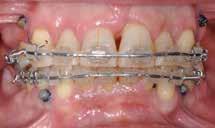

Ortodontisk behandling af patienter med parodontitis kan ofte foretages sikkert ved at følge en systematisk tilgang, der omfatter 1) inflammationskontrol, 2) ortodontisk korrektion og 3) livslang vedligeholdelse. Inden behandlingen påbegyndes, skal parodontiet generelt være sundt med pocher på maksimalt 4 mm og et plak- og blødningsindeks under 10 %. Restfæstet skal være tilstrækkeligt til at modstå behandlingen, som udføres med kontrollerede kraftsystemer. Målet er at forbedre æstetik og opnå normal funktion, som kan vedligeholdes på lang sigt samt facilitere restaurerende behandling.

Der planlægges alignerbehandling af begge kæber med intrusion af 1+1 og 2,1-1,2, nivellering af trangstilling UK med interproksimal reduktion (IPR) (Fig. 2 A, B) og senere IPR OK for reduktion af dark triangles mellem incisiverne efter nivellering. Patienten instrueres i at benytte alignere 20-22 timer/ dag med alignerskift hver 7. dag, og patienten ses hver 3.-8. uge under forløbet. Den første alignerserie består af 16 alignere for nivellering OK/UK og IPR i UK (Fig. 2). Efter denne serie planlægges IPR mellem incisiverne i OK for reduktion af dark triangles (Fig. 3) samt yderligere intrusion af OK og UK-fronten i 12 refinement-alignere. Patienten udviser god kooperation og er meget tilfreds med alignerapparaturet, som er mindre synligt end det faste apparatur (Fig. 4).

Behandlingen afsluttes med yderligere refinement-alignere for finindstilling af okklusionen, og efter 11 måneders ortodontisk behandling er der opnået normale relationer i alle tre